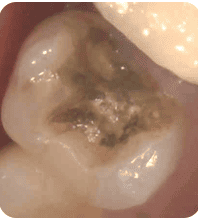

↓金属の中で広がっていた2次虫歯